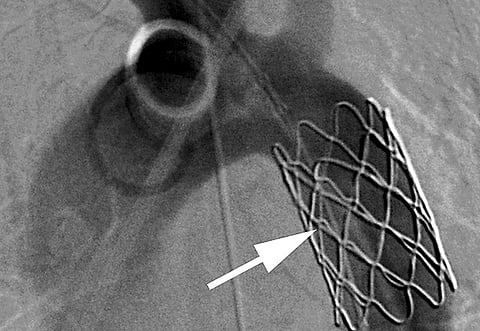

A specially designed stent was inserted into the damaged area to close the tear and stop the blood from leaking through the aorta wall. The stent was made of a platinum frame that was coated with 24-karat gold and covered with a special tissue. A number of these stents had been brought to the hospital from the US just days prior to the procedure, Dr Hamdan said.